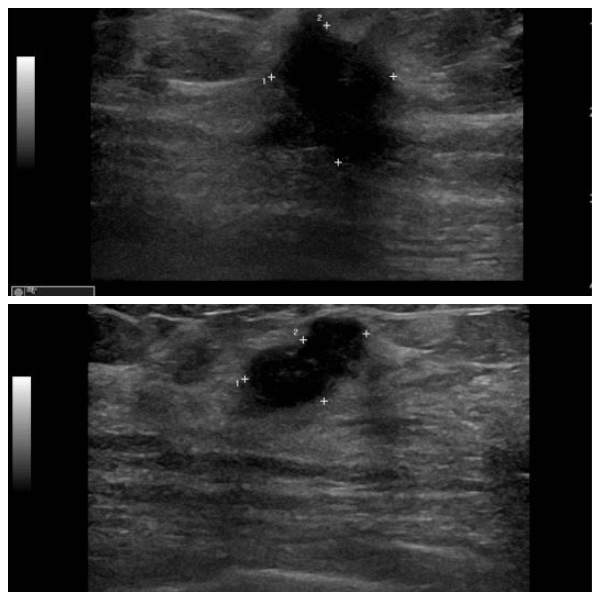

상기환자    좌측에 만져지는 멍울로 내원하신 60대 여성분으로  좌측 11시 방향에

만져지는  멍울 조직검사 시행하여  좌측 침윤성 유관암 진단 되었습니다.